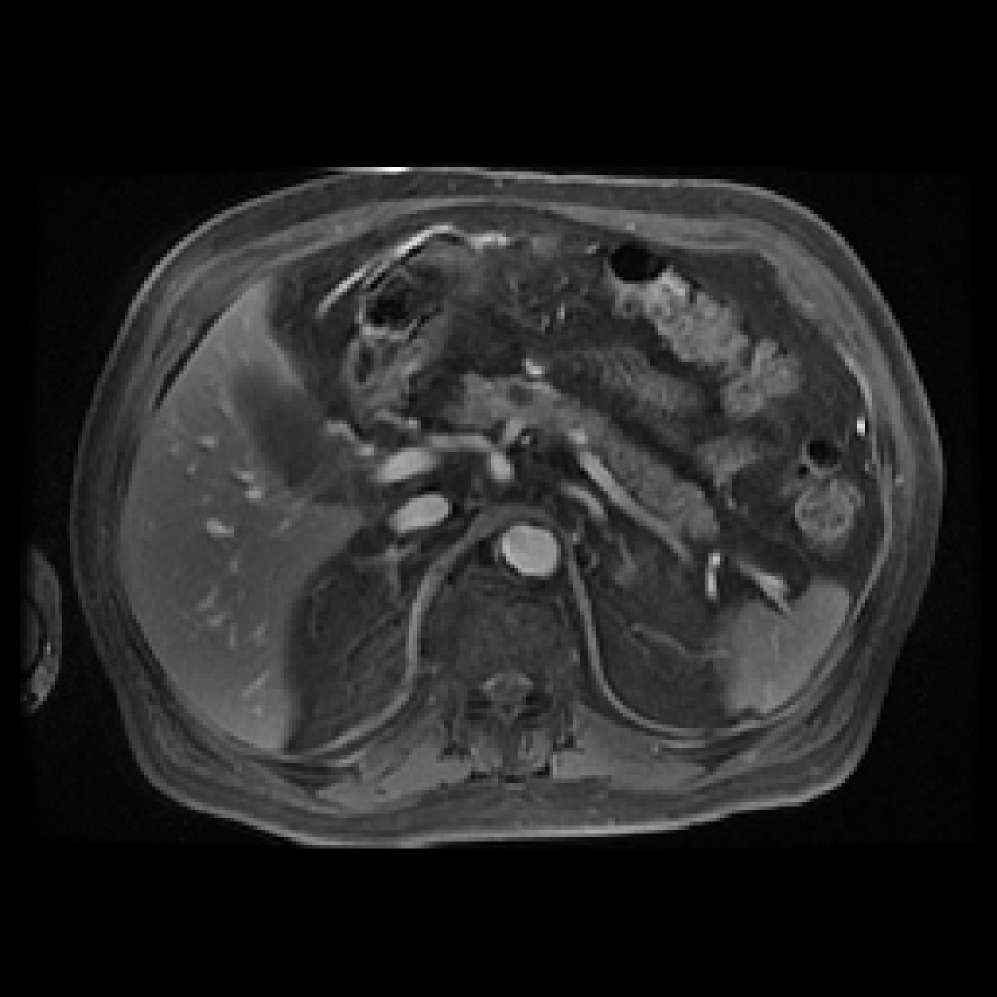

Accurate pancreas segmentation is a critical prerequisite for precise cyst analysis and classification. Recently, we developed PanSegNet [zhang2025large], a novel segmentation architecture incorporating linear self-attention layers [zhang2022dynamic] within the nnUNet framework [isensee2021nnu] to enhance global information modeling capabilities while maintaining computational efficiency (Fig. 1). PanSegNet demonstrated exceptional segmentation performance across both T1W and T2W modalities, achieving mean dice scores of 86.817.30% and 89.626.38%, respectively (Table 1, Fig. 2b-c). This performance significantly exceeded that of Swin-UNETR [hatamizadeh2021swin], one of the most used state-of-the-art transformer-based medical segmentation models, which achieved dice scores of 79.091.40% and 76.290.66% for T1W and T2W, respectively (). In this study, we integrated PanSegNet into our Cyst-X engine along with a classifier for risk prediction. In Section 2.2, we show that the choice of segmentation model affects the classification results. The performance advantage of PanSegNet was consistent across all seven medical centers, demonstrating robust generalization despite variations in imaging protocols and equipment (Table 1). This cross-institutional reliability is particularly important for clinical applications, where model performance must remain consistent regardless of imaging site or acquisition parameters.

We evaluated multiple approaches for IPMN risk classification, comparing radiomics-based methods with deep learning models, and benchmarking against both established clinical guidelines and expert radiologist assessments. Our 3D DenseNet-121 model achieved superior performance in distinguishing high-risk from low-risk and no-risk IPMNs (Table 2). In a direct comparison with the Kyoto Criteria [ohtsuka2024international], our model demonstrated significantly improved diagnostic accuracy (AUC=82.371.02% vs. AUC75%, ) for T2W images. Notably, the performance improvement was most substantial in detecting high-risk lesions (sensitivity 87.8% vs. 64.1%, ), which is clinically critical for preventing missed opportunities for early intervention. To further interpret the model’s feature representation, we performed t-SNE visualization of both the input images and the hidden states from the DenseNet-121. As shown in Fig. 3, input features show limited separation across risk classes, while the learned embeddings exhibit improved clustering by risk category. This indicates that the model successfully learns discriminative representations for IPMN risk stratification.

When compared with the visual assessments of three expert radiologists, our models demonstrated superior accuracy in both no/low-risk and high-risk cases. As shown in Table 3, the DenseNet-121 model with probability fusion achieved a no/low-risk classification accuracy of 94.66% and a high-risk accuracy of 47.18%, outperforming the radiologists’ average accuracies of 93.91% and 46.01%, respectively. While this overall performance suggests that Cyst-X surpasses expert-level assessments, a more nuanced interpretation is warranted. Notably, Radiologist 2’s performance demonstrates a tendency toward high Negative Predictive Value (NPV)at the expense of sensitivity (i.e., substantially lower accuracy at just 32.39%), which risks missing malignant cases. In contrast, our model maintained a more balanced performance across risk categories, demonstrating both strong sensitivity and specificity. This balance suggests that Cyst-X is not only more accurate overall but also potentially more reliable in clinical decision-making, where both under- and over-diagnosis carry significant consequences. For visual explainability of classification results, visual saliency-based methods are often used, although most of such methods are not true explanation methods, but show mostly learned patterns in the image region in correlation to the result. For this purpose, GradCAM [selvaraju2017grad] and Information Bottleneck Attribution (IBA) [schulz2020restricting, demir2021information] based visualizations were generated (See Supplementary materials).